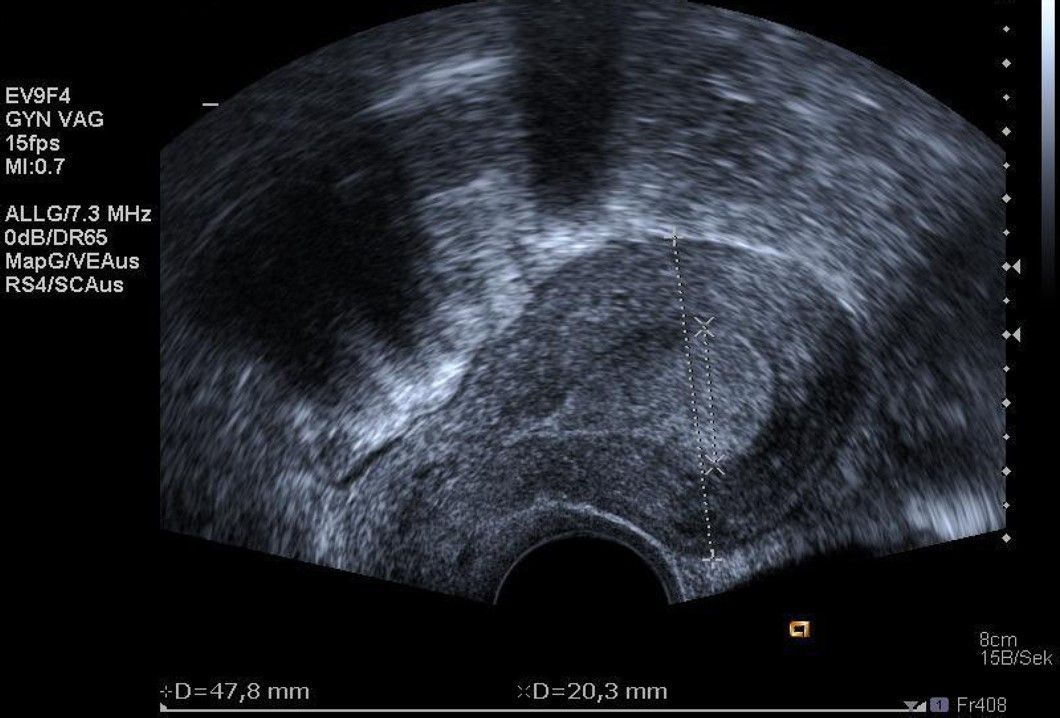

Die Diagnosestellung erfolgt in aller Regel mittels transvaginalem (durch die Scheide) Ultraschall. Nur in Ausnahmefällen ist eine MRT-Untersuchung notwendig.

Bei der Gebärmutterspiegelung wird die Gebärmutterhöhle mit Kochsalzlösung aufgedehnt. Eine Kamera mit integrierter Elektroschlinge wird in die Gebärmutter eingeführt. Die vorhandenen Myome können nun schrittweise unter Sicht abgetragen werden. Mittels modernsten Ultraschalluntersuchungen werden die Myome während der Operation noch einmal genau dargestellt. Bei sehr großen Befunden können zwei Operation zur kompletten Myomentfernung notwendig sein.